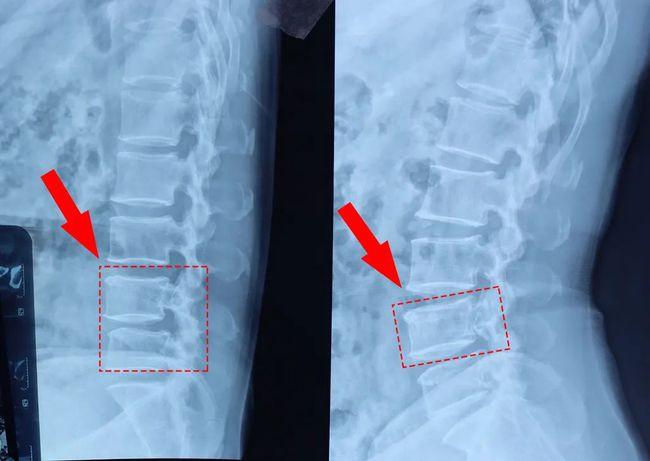

腰椎x线片: 腰椎术后,l3/4-l4/5行腰椎减压植骨融合内固定术